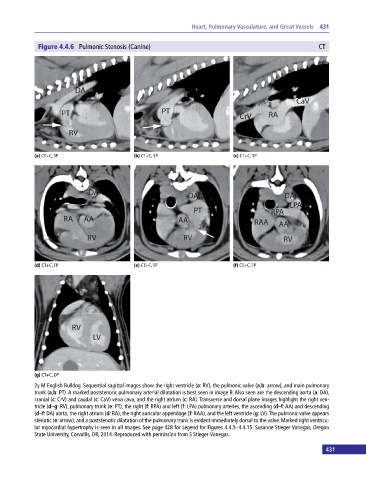

Figure 4.4.6 Pulmonic Stenosis (Canine) CT

(a) CT+C, SP (b) CT+C, SP (c) CT+C, SP

(d) CT+C, TP (e) CT+C, TP (f) CT+C, TP

(g) CT+C, DP

2y M English Bulldog. Sequential sagittal images show the right ventricle (a: RV), the pulmonic valve (a,b: arrow), and main pulmonary

trunk (a,b: PT). A marked poststenotic pulmonary arterial dilatation is best seen in image B. Also seen are the descending aorta (a: DA),

cranial (c: CrV) and caudal (c: CaV) vena cava, and the right atrium (c: RA). Transverse and dorsal plane images highlight the right ven-

tricle (d–g: RV), pulmonary trunk (e: PT), the right (f: RPA) and left (f: LPA) pulmonary arteries, the ascending (d–f: AA) and descending

(d–f: DA) aorta, the right atrium (d: RA), the right auricular appendage (f: RAA), and the left ventricle (g: LV). The pulmonic valve appears

stenotic (e: arrow), and a poststenotic dilatation of the pulmonary trunk is evident immediately dorsal to the valve. Marked right ventricu-

lar myocardial hypertrophy is seen in all images. See page 428 for Legend for Figures 4.4.5–4.4.15. Susanne Stieger‐Vanegas, Oregon

State University, Corvallis, OR, 2014. Reproduced with permission from S Stieger‐Vanegas.